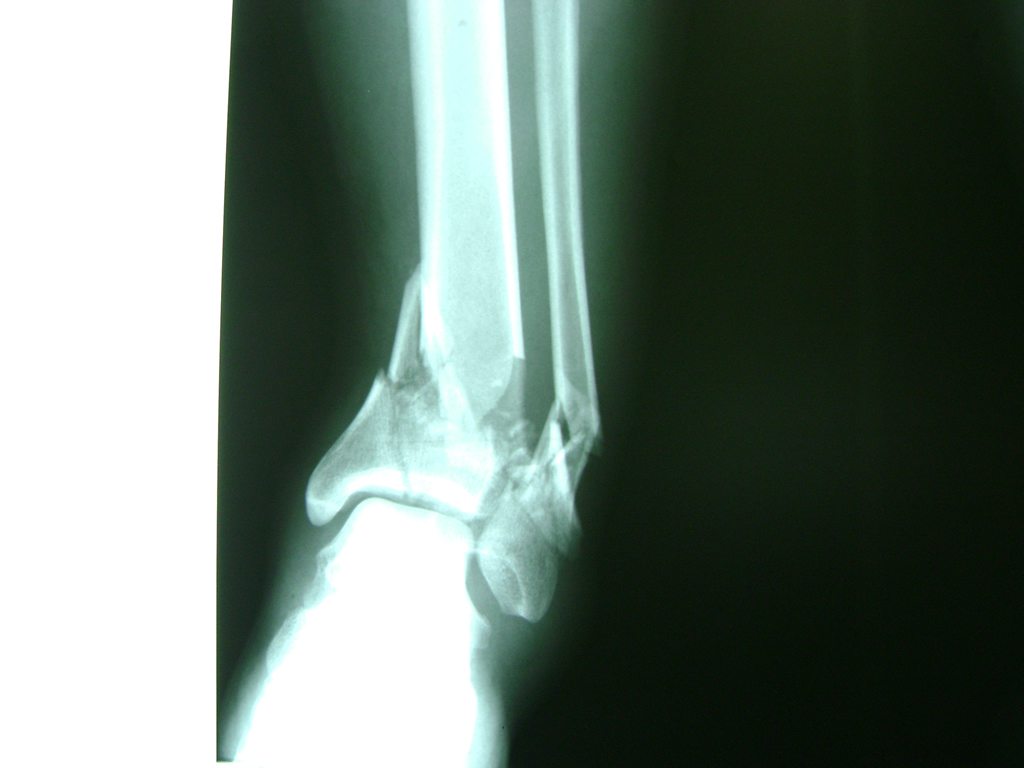

Una fractura de tobillo es la rotura de uno o más de los huesos del tobillo. Estas fracturas pueden ser:

- Parciales (el hueso está sólo parcialmente fisurado, no del todo).

- Completas (el hueso está perforado y está en 2 partes).

- Producirse en uno o ambos lados del tobillo.

Algunas fracturas de tobillo pueden requerir cirugía si:

- Los extremos de los huesos están desalineados entre sí (desplazados).

- La fractura se extiende hasta la articulación del tobillo (fractura intra-articular).

- Los tendones o ligamentos (tejidos que sujetan los músculos y los huesos entre sí) están rotos.

- El médico cree que sus huesos probablemente no sanen apropiadamente sin cirugía.

- El médico considera que la cirugía puede permitirle una recuperación más rápida y confiable.

- En los niños, la fractura involucra la parte del hueso del tobillo donde el hueso está creciendo.

Cuando se necesita cirugía, es probable que esta implique el uso de clavijas de metal, tornillos o placas para sostener los huesos en su lugar mientras la fractura se consolida. Los elementos de soporte pueden ser temporales o permanentes.